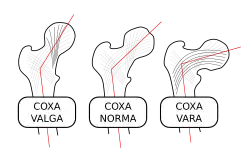

Femoral neck angle

The angle between the longitudinal axes of the femoral neck and shaft, called the caput-collum-diaphyseal angle or CCD angle, normally measures approximately 150° in newborn and 126° in adults (coxa norma).[21]

An abnormally small angle is known as coxa vara and an abnormally large angle as coxa valga. Because changes in shape of the femur naturally affects the knee, coxa valga is often combined with genu varum (bow-leggedness), while coxa vara leads to genu valgum (knock-knees).[22]